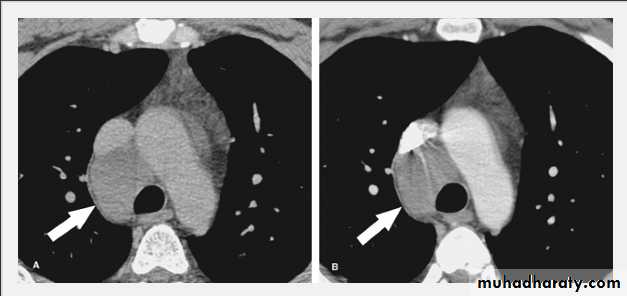

Tension pneumothorax.

On a posteroanterior chest x-ray (A), the left hemithorax is very dark or lucent because the left lung has collapsed completely (white arrows).

The tension pneumothorax can be identified because the mediastinal contents, including the heart, are shifted toward the right, and the left hemidiaphragm is flattened and depressed. A computed tomography scan done on a different patient with a tension pneumothorax (B) shows a completely collapsed right lung (arrows) and shift of the mediastinal contents to the left.